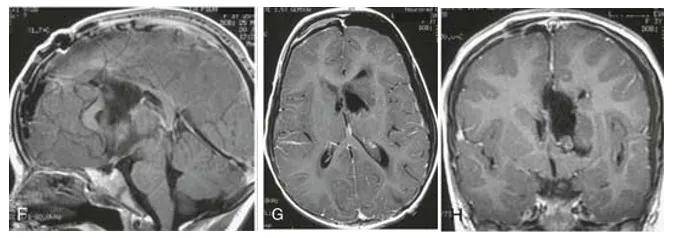

巨大的侧脑室占位

然而,意外情况突然发生。就在家人四处咨询期间,文文的病情出现了急剧变化。她突发意识模糊,继而陷入昏迷状态。接到家人电话通知时,文文母亲的心情瞬间沉入谷底。她迅速赶往急诊室,医生告知文文出现了梗阻性脑积水的症状,必须立即接受手术干预。时间紧迫,不容犹豫,文文母亲只能目送女儿被推进手术室。手术很快完成,医生首先为文文放置了外部脑室引流管以缓解梗阻性脑积水,但导致积水的根本病因——肿瘤,并未被清除,因此后续手术依然势在必行。

最终,这场由巴教授主刀的手术取得了成功。在术中磁共振与术中神经导航技术的辅助下,肿瘤被精准地完全切除。术后病理报告证实为室管膜瘤,分级为3级。术后,文文未出现任何新的神经功能损伤。鉴于肿瘤的恶性性质,她后续仍需接受放疗与化疗,以控制肿瘤复发的风险。